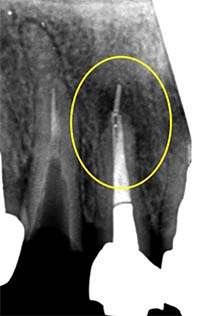

当院での治療例です。ご来院された(初診時)治療前の状態と根充後(治療後)の状態をレントゲンとCTで確認すると次のようになります。

しっかりと根充されていることがCTにより確認すことができます。